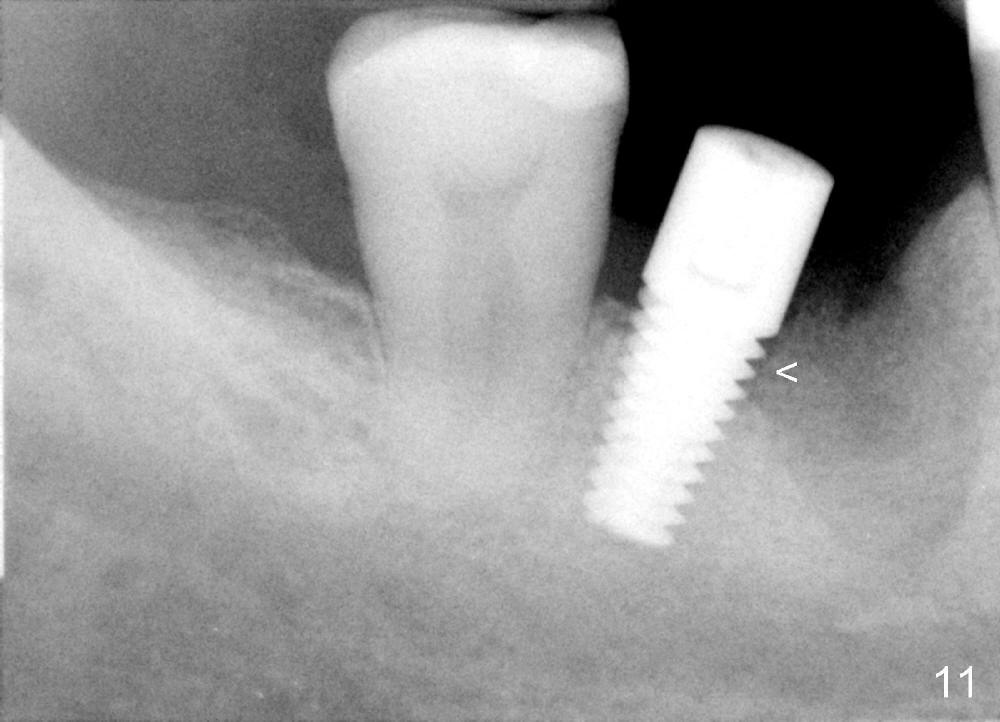

When the perio dressing is removed in office 24 days postop (Fig.9), the rough surface of the implant (R) is exposed buccally. Normally the smooth surface should contact the gingiva (S). Lingually implant/gingiva position is within normal limit (Fig.10). The patient returns for restoration 4 months postop (Fig.11,12). There is bone formation in the mesial socket and new bone appears to have grown toward the implant (Fig.11 <). A straight abutment appears to be in the middle of the edentulous space (Fig.12 A). But it is difficult to seat the crown. Three months post cementation, the patient complains of food impaction mesially (Fig.10 ^), although bone density continues to increase in the mesial socket and there is no mesial coronal thread exposure (*). Retrospectively the implant should be tried to be placed in the septum as much as possible to have a favorable restorative axis (Fig.14). The crown is re-fabricated with larger mesial contact area. It is temporarily cemented because of slightly loose distal contact (Fig.15). A few days later, the patient requests permanent cementation, because although the distal contact is loose, it is easy to remove food. Mesial food impaction is less likely, but it is more difficult to be removed.